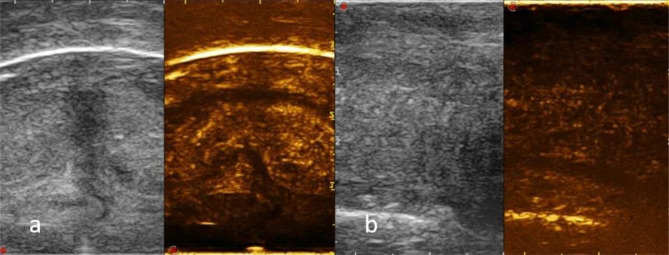

Fig. 2.

a ECD shows millimetric inhomogeneous hypoechoic and hypervascular area (arrowhead) centered in the ventral portion of the left CC; b mucosal and subcutaneous tissue swelling (arrow)